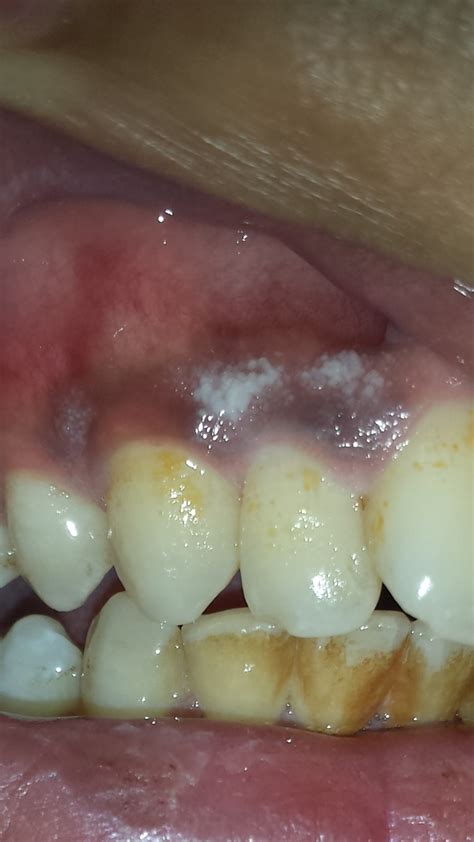

Discovering white sores on the gums can be an alarming experience, often causing immediate discomfort and concern about underlying health issues. While the mouth is home to a vast ecosystem of bacteria, the appearance of white lesions, patches, or spots on your gum tissue usually serves as a signal from your body that something is out of balance. Whether these spots are triggered by simple physical trauma, nutritional deficiencies, or infections, identifying the cause is the first step toward effective relief. Understanding the different conditions associated with these oral anomalies is essential for maintaining proper dental hygiene and overall physical health.

The appearance of white sores on the gums can be attributed to several different medical and environmental factors. It is helpful to distinguish between benign, short-term issues and conditions that may require professional intervention. Below are the most frequent culprits behind these oral lesions:

• Canker Sores (Aphthous Ulcers): These are perhaps the most common cause. They are small, shallow, white or yellow-centered ulcers surrounded by a red border. They are not contagious but can be quite painful.

• Oral Thrush (Candidiasis): Caused by an overgrowth of the Candida fungus, this condition typically manifests as creamy white, raised lesions that can be wiped away, often leaving behind red, tender tissue.

• Leukoplakia: These are thick, white patches that form on the gums, the inside of cheeks, or the tongue. While often benign, they can sometimes be precursors to oral cancer and should be monitored by a dentist.

• Gingival Abscess: A localized collection of pus in the gum tissue can appear as a white or yellowish pimple-like bump, often signaling a deep infection near the tooth root.

• Traumatic Injury: Sharp food particles, aggressive brushing, or ill-fitting dental appliances can cause small white sores or abrasions on the sensitive gum tissue.